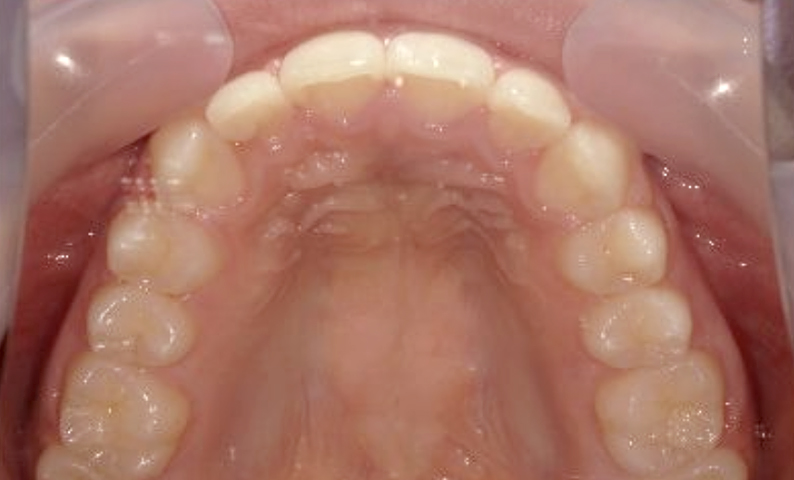

症例_007 上顎だけの部分矯正

治療期間:7ヶ月金額:27万円+税女性出っ歯前歯1本上の前歯だけ